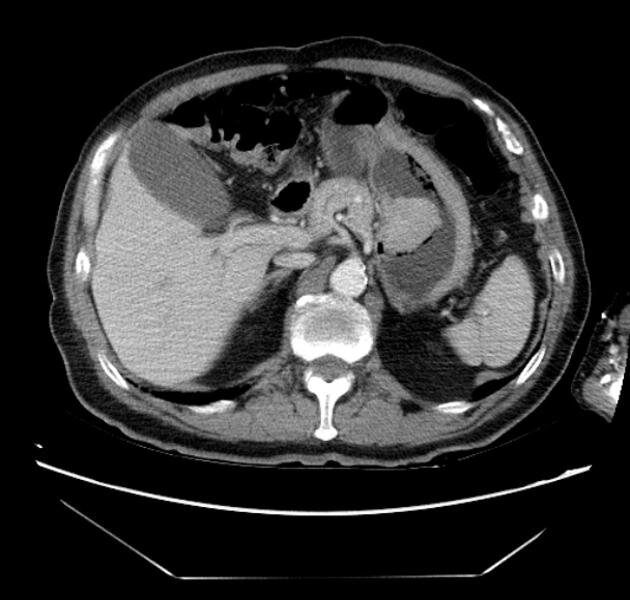

Что покажет компьютерная томография желудка

В этом состоит преимущество КТ желудка и кишечника в СПб перед эндоскопией, которая дает возможность увидеть лишь внутреннюю поверхность органа. Изменения характеристик органа, таких как толщина и эластичность, можно точно отследить с помощью КТ кишечника и желудка. На томографических снимках будут хорошо отмечены все, даже самые мелкие, очаговые уплотнения и объемные образования.

При помощи КТ эффективно обнаруживают различные нарушения, вызывающие сужение просвета органа, такие как стриктуры и стенозы. КТ желудочной области и кишечного тракта хорошо подходит для диагностики зло- и доброкачественных новообразований в брюшной полости. Особая диагностическая ценность этого метода заключается в том, что благодаря КТ желудка с контрастом удается четко определить размеры опухоли, локацию, степень инвазии и стадировать рак. В случае присутствия онкологического процесса в организме томография способна выявить метастазирование в лимфатические узлы ключичной, забрюшинной и паховой области. КТ показана для дифференциальной диагностики некоторых системных заболеваний, например, язвенного колита и болезни Крона.

Компьютерная томография является методом первичной диагностики доброкачественных новообразований и рака желудка. Показаниями к проведению к компьютерной  томографии пациентам с различными опухолевыми заболеваниями желудка являются уточнение вопросов распространенности опухолевой инфильтрации, как в стенке, так н на соседние органы и ткани, а также оценка состояния регионарных лимфатических узлов и выявления отдаленных метастазов в паренхиматозные органы брюшной полости. Чувствительность метода в выявлении доброкачественных новообразований составляет 96,8%, что позволяет с высокой  точностью диагностировать истадировать онкологические заболевания ЖКТ.

Далее пациент помещается на стол томографа. Процедура диагностики не приносит боли пациенту и ограничивается по времени несколькими минутами. Двигаться в ходе 5-7-минутного исследования нельзя, для того чтобы снимок был четким. Во время скрининга детекторы в кольце гентри МСКТ делают несколько оборотов вокруг тела обследуемого. Так получаются многочисленные сканы. На этих томограммах желудок и кишечник показаны в виде послойных срезов в нескольких проекциях, из которых компьютер способен создать объемную проекцию органов для четкой их визуализации. Трехмерная модель брюшной полости позволяет рассматривать патологии со всех ракурсов, что повышает точность диагностики.